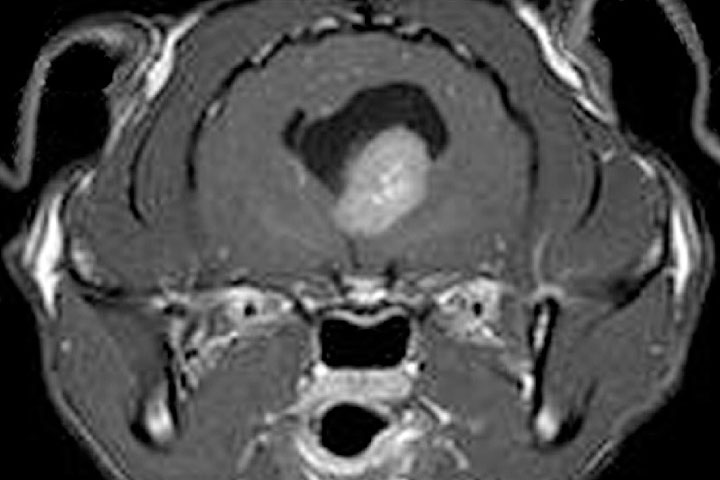

It is the most common primary brain tumour in dogs and cats. Meningiomas are extra-axial, well demarcated, large masses. As derived from the leptomeninges, they sit between the dura and the brain.

On MRI, they appear as well defined, homogeneous, broad base masses with strong and uniform contrast enhancement.